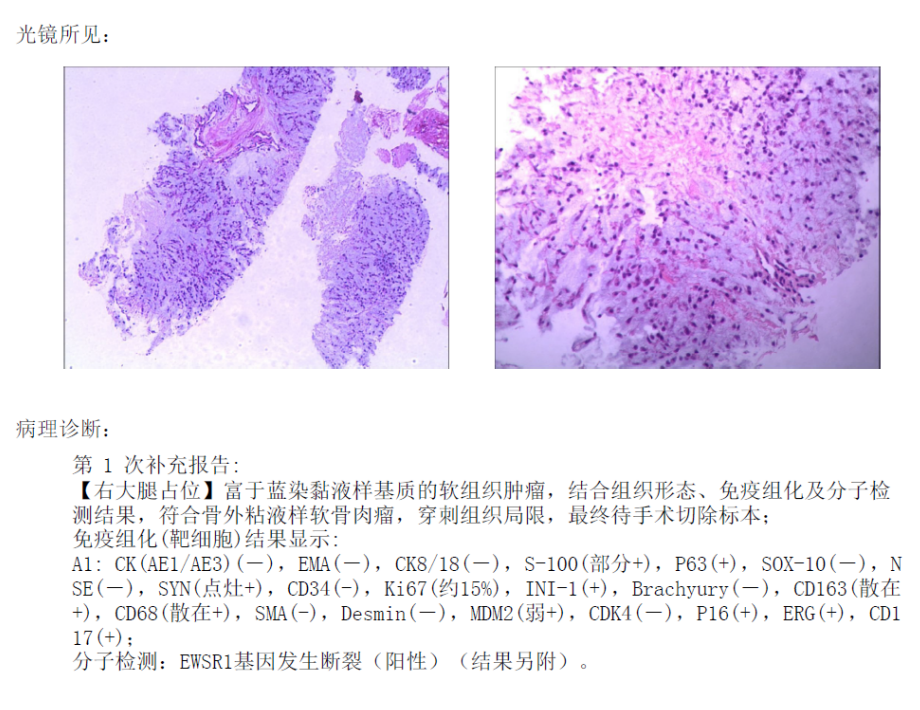

病理诊断:骨外粘液样软骨肉瘤

骨外粘液样软骨肉瘤 ( extraskeletal myxoid chondrosarcoma,EMC) 是一种罕见的低度恶性间充质肿瘤,约占所有软组织肉瘤的 3% ,其特征是组织中含有丰富的粘液样基质。该肿瘤生长缓慢,局部复发率和转移率较高。由于 EMC 十分少见, 临床表现不具有特征性,术前早期诊断困难。该病是一种具有自身特征的肿瘤实体,与典型的软骨肉瘤有不同的临床和组织病理学特征, 最早被报道为低度恶性的肿瘤,据最近的统计数据 显示,EMC 患者有较高的局部复发、转移率和死亡率,因此被归类为中度恶性肿瘤。该病的好发年龄为 50 岁,男女比例为 2: 1,最常见的发病部位是四肢深部软组织,尤其是大腿,其他部位如颈部、 足部、眼眶和会阴也有报道。